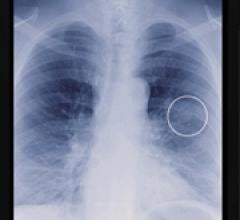

November 23, 2010 — Two recently FDA-approved computer-aided detection (CAD) products will be displayed at RSNA Chicago ...